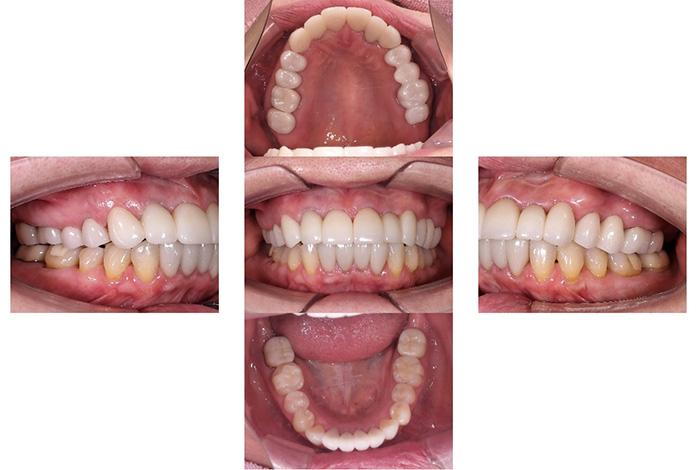

Before

After

前歯の見た目と噛み合わせのバランスを整えたケース

「前歯が強くかみ込んでいる気がする」「歯並びだけでなく、噛み合わせも気になる」

今回の患者様は、ディープバイト(過蓋咬合)による前歯の見た目と噛み合わせを気にされて来院されました。ディープバイトとは、上の前歯が下の前歯に深く重なっている噛み合わせのことで、見た目の問題だけでなく、前歯や顎への負担につながることがあります。

本症例では、マウスピース型矯正装置(インビザライン)を用いて治療を行いました。合計84枚のアライナーを使用し、歯並びだけでなく咬合の深さにも配慮しながら治療を進めました。

治療後は、前歯の見た目のバランスが整い、噛み合わせも改善しました。